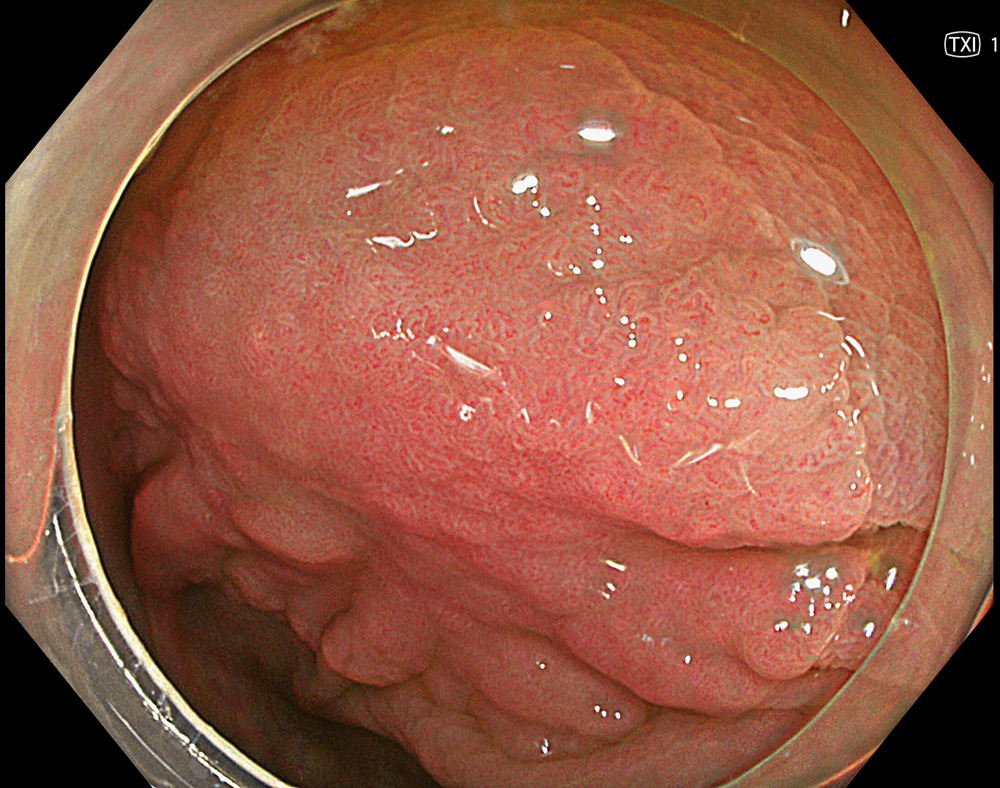

2. LST-NG with TXI (Mode 1)

TXI mode 1 enhances the lesion by combining texture, brightness, and color tone enhancement, improving visualization of surface structure and lesion margins compared with white light imaging.